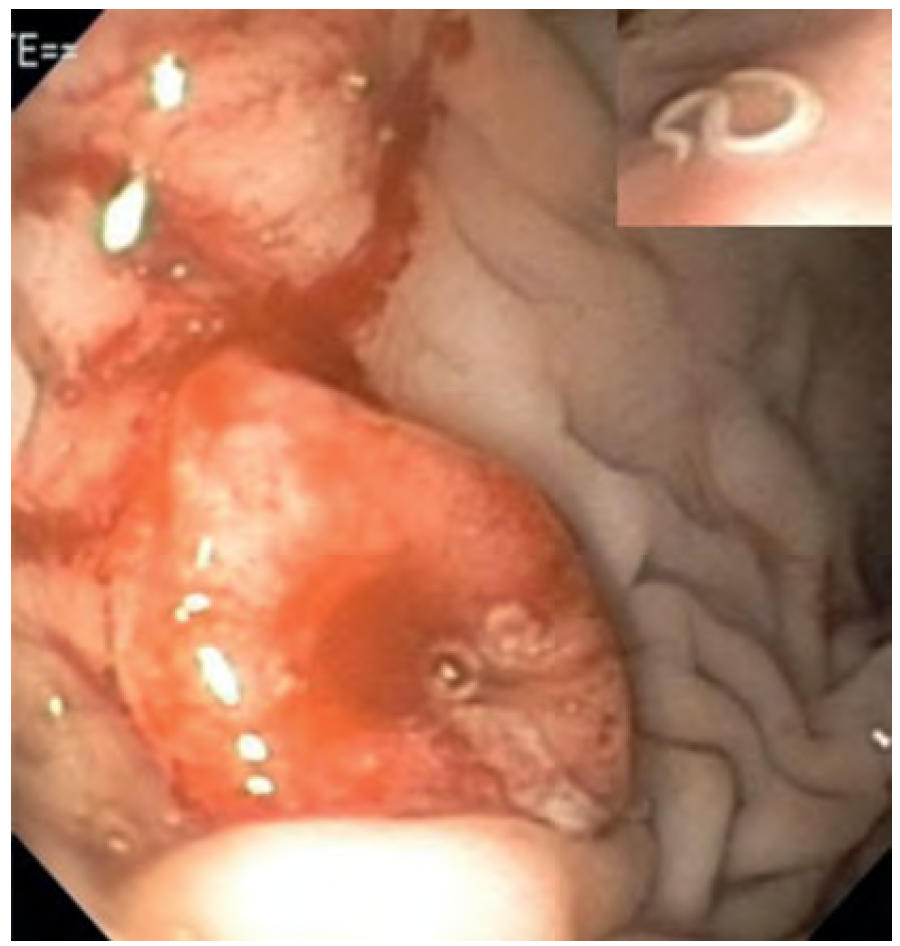

- 胃肠道内窥镜检查:在内窥镜检查过程中可以检测到黏膜糜烂和水肿(图2)。胃镜检查可能用于移除胃内异物。

- 泡翼线虫感染有时只能通过内窥镜检查诊断(图3)。

图2. 胃镜图像显示一只患有急性胃炎的狗因糜烂导致的多处黏膜表面出血。

图3. 内窥镜观察胃黏膜,显示一只患有寄生虫性胃炎的狗的结节状病变(插图:泡翼线虫感染)。